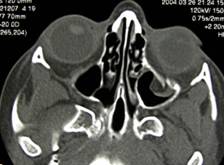

Orbital fractures 2

Baseline fracture involving the left orbit